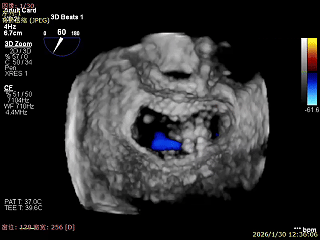

3D Enface下组织桥稳定残余外侧前叶脱垂

3D Enface上彩可见夹子内侧无反流,残余外侧反流

3D Enface下组织桥稳定无反流

夹子释放后,反流基本消失